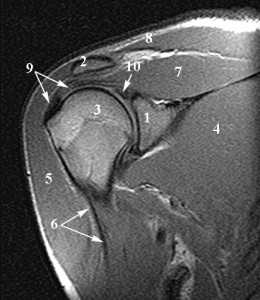

Анатомия плечевого сустава. Т1-зависимая МРТ в корональной плоскости. Обозначения: 1 -суставная (гленоидная) впадина, 2 - ключица, 3 -головка плечевой кости, 4 - подлопаточная мышца, 5 - дельтовидная мышца, 6 - длинная головка сухожилия двуглавой мышцы плеча, 7 - надостная мышца, 8 - трапецевидная мышца, 9 - сухожилие надостной мышцы, 10 - верхняя губа.

Костные структуры плечевого сустава.

Схема костных структур, образующих плечевой сустав.